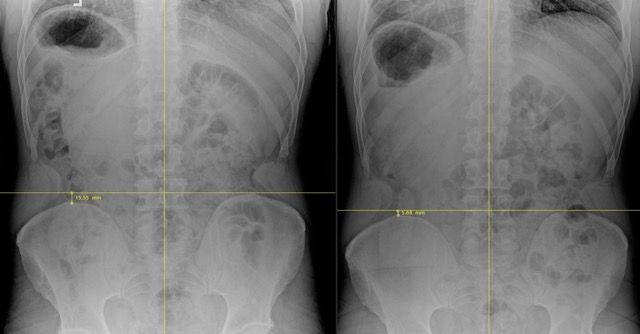

We use detailed X-rays to identify exactly what's happening in your spine. This gives us a precise starting point and allows us to track your improvement with objective measurements.

We take follow-up X-rays to show you the actual structural changes in your spine. The images don't lie – you'll see real improvement, not just temporary pain relief.

Our before and after X-rays show significant structural improvements in spinal alignment. What many doctors consider "normal degeneration" can actually be improved with the right approach.